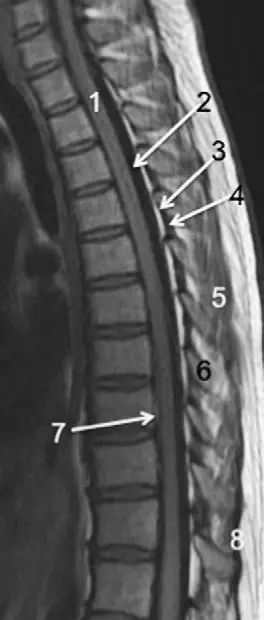

胸,腰椎mri解剖图谱,新手必备